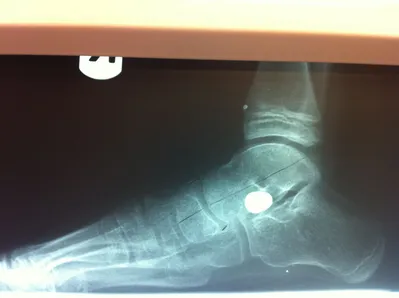

Below are x-rays of a foot pre-operatively (left) where the black line indicates and plantarflexed (downward directed) talus bone and post-surgical repair with a subtalar joint implant and lenthening of the calf muscle which allows the calcaneus (heel bone) to set underneath the talus and the implant keeps the talus from subluxing off the calcaneus and now the talus is more inline with the front of the foot (right).